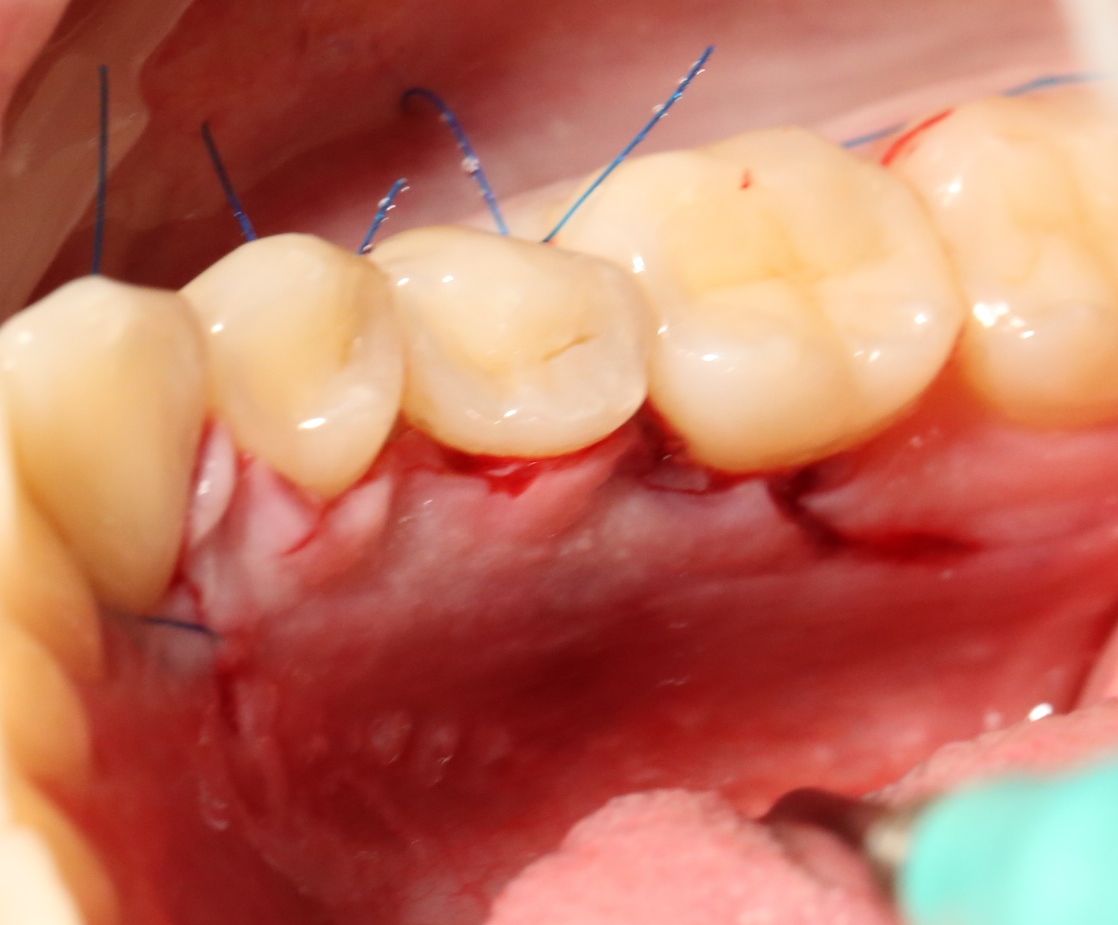

Благодаря сделанному нами разрезу, мы можем вывести узелки на внешнюю сторону альвеолярного отростка, что будет удобнее и комфортнее для пациента:

Операция закончена.

Вот фотография послеоперационной раны через пару дней:

Так, друзья, выглядит нормальная послеоперационная рана. Со швами я угадал. Это, кстати, Prolene 5-0.